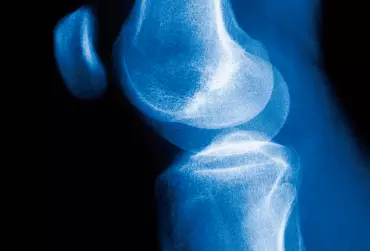

Rehabilitacja po operacyjnym leczeniu łąkotki stawu kolanowego

Łąkotki stawu kolanowego to dwie włóknisto-chrzęstne struktury, których zadaniem jest pogłębienie i wypełnienie powierzchni stawowej. Charakteryzują się półksiężycowatym kształtem. Obrażenia łąkotek stawu kolanowego występują zazwyczaj u młodych ludzi uprawiających sport. U osób starszych, u których struktura łąkotek jest zazwyczaj osłabiona, do ich uszkodzenia może dojść nawet podczas codziennych czynności, np. przysiadu.